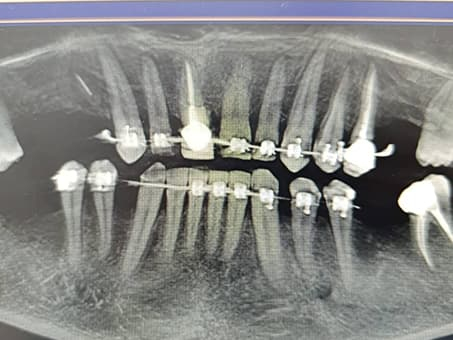

Современная стоматология имеет два разных способа удаления зуба, цена на которые также отличается:

Простое удаление. В этом случае речь идет об удалении зубов, которые хорошо просматриваются в ротовой полости. Как правило, процедуру выполняет специалист широкого профиля.

Удаление зуба происходит следующим образом: с помощью элеватора врач расшатывает больной зуб, а затем щипцами его удаляет. Простое удаление проводится с обязательным применением местной анестезии.

Хирургическое удаление. Это сложная процедура, к которой прибегают в случае повреждения (перелома) зуба на линии десны или ниже, а также в случае ретинированного зуба.

Это хирургическая операция, которую чаще всего проводит челюстно-лицевой хирург, реже - стоматолог широкого профиля. Для удаления проблемного зуба проводится рассечение десны и после этого извлекается зуб – целый или по частям.